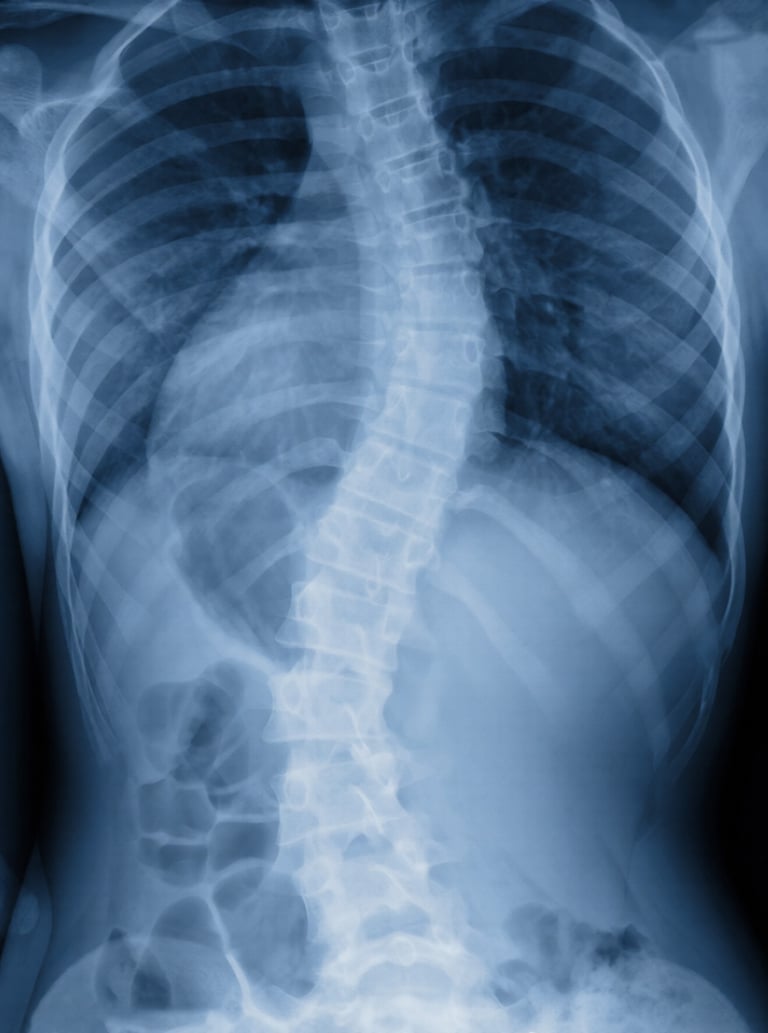

Scoliosis Spine Surgery

A specialized procedure to correct abnormal curvature of the spine caused by scoliosis. Using advanced instrumentation such as rods, hooks, and screws, the spine is realigned and stabilized—often accompanied by spinal fusion to maintain correction. The goal is to reduce deformity, prevent progression, and improve posture, balance, and quality of life.